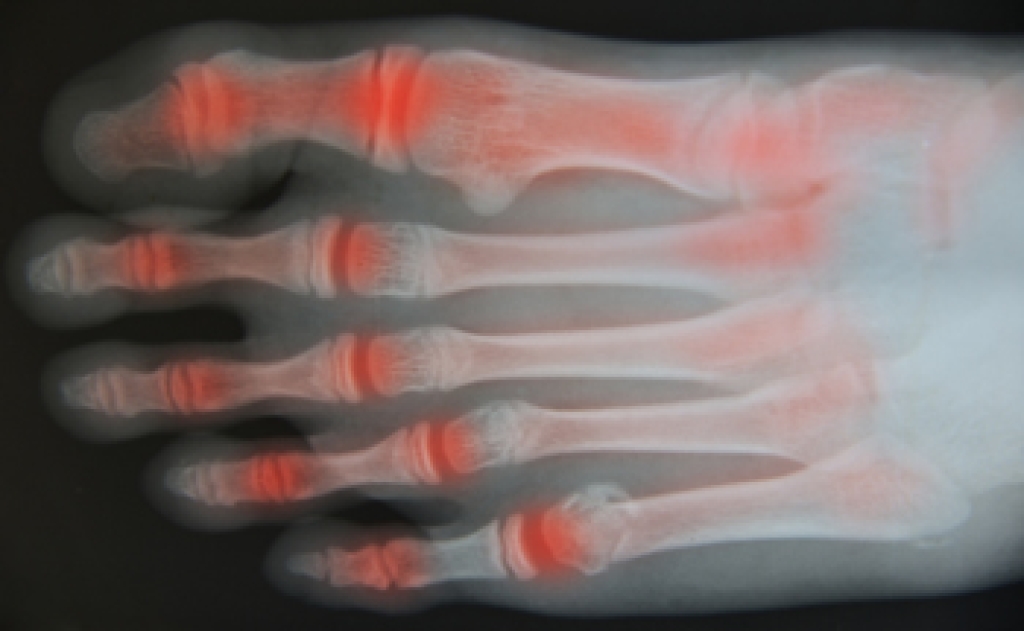

Podiatrists often perform two tests – blood tests and x-rays – when trying to diagnose bunions, especially in the early stages of development. Blood tests help determine if the foot pain is being caused by something else, such as arthritis, while x-rays provide a clear picture of your bone structure to your provider.